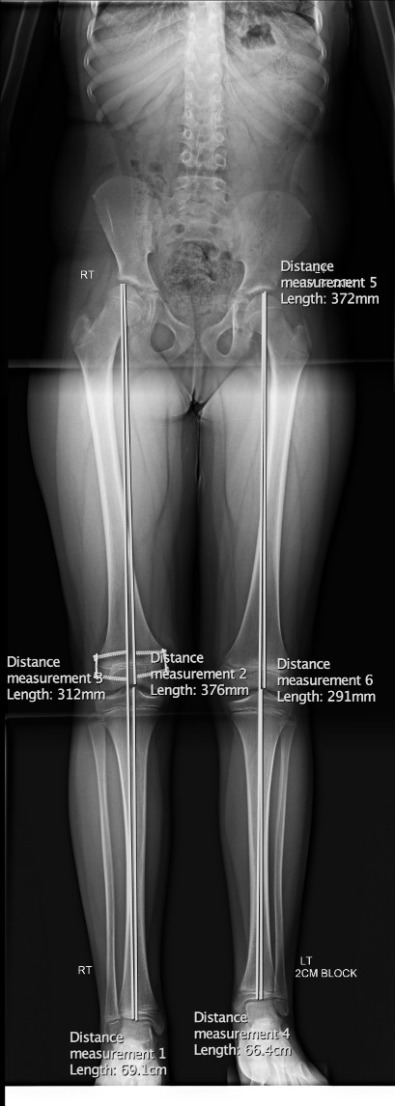

The x-rays below show a case with shortening of the lower limbs (epiphysis).